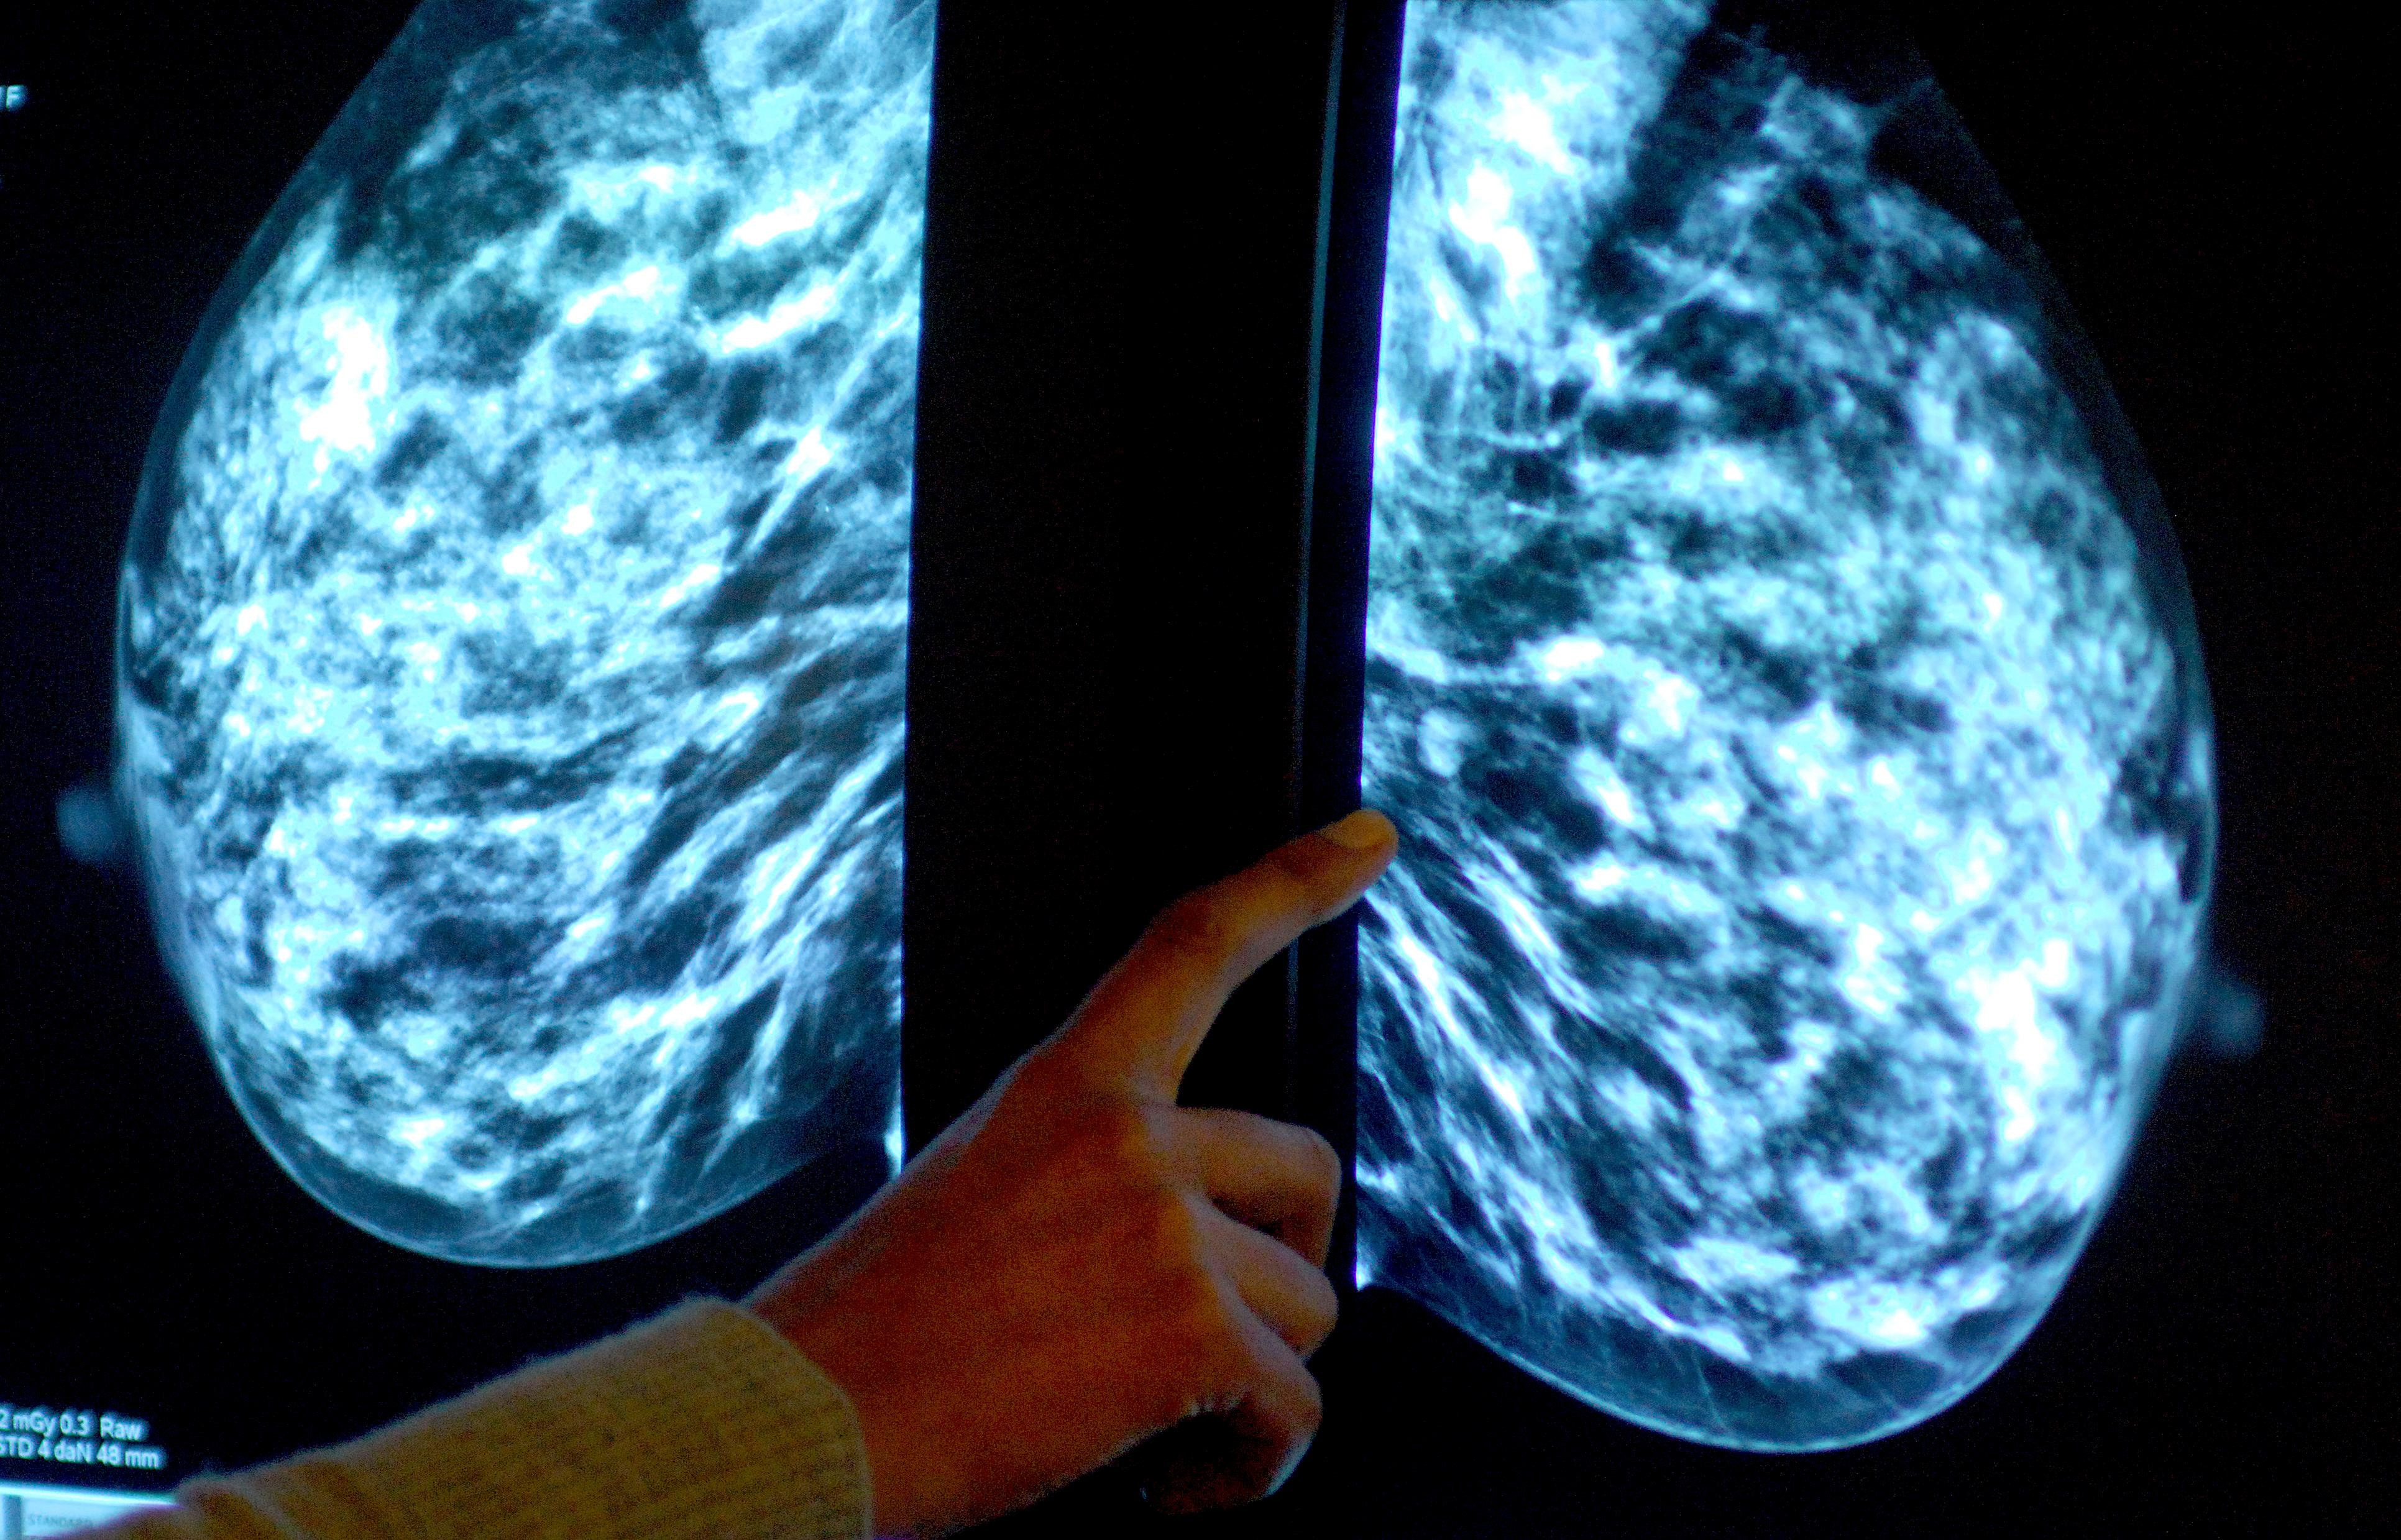

Anyone registered with a GP as female will be invited for NHS breast screening every three years between the ages of 50 and 71.

NHS England figures show 47,240 of the 72,250 people invited for a screening in the former NHS Devon CCG had a test in the year to March this year.

It meant uptake of the screening stood at 65% – down from 69% the year before, and below pre-pandemic levels of 74% in 2019-20.